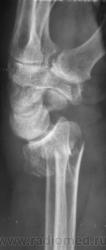

Случай 3. Пациент направлен врачом хирургом на рентгенографию лучезапястного сустава.